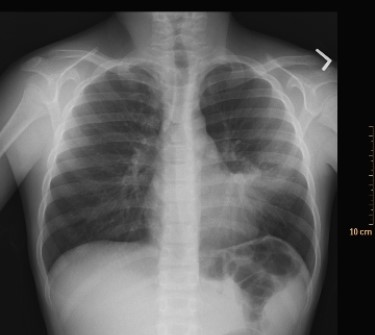

What condition does the image depict?